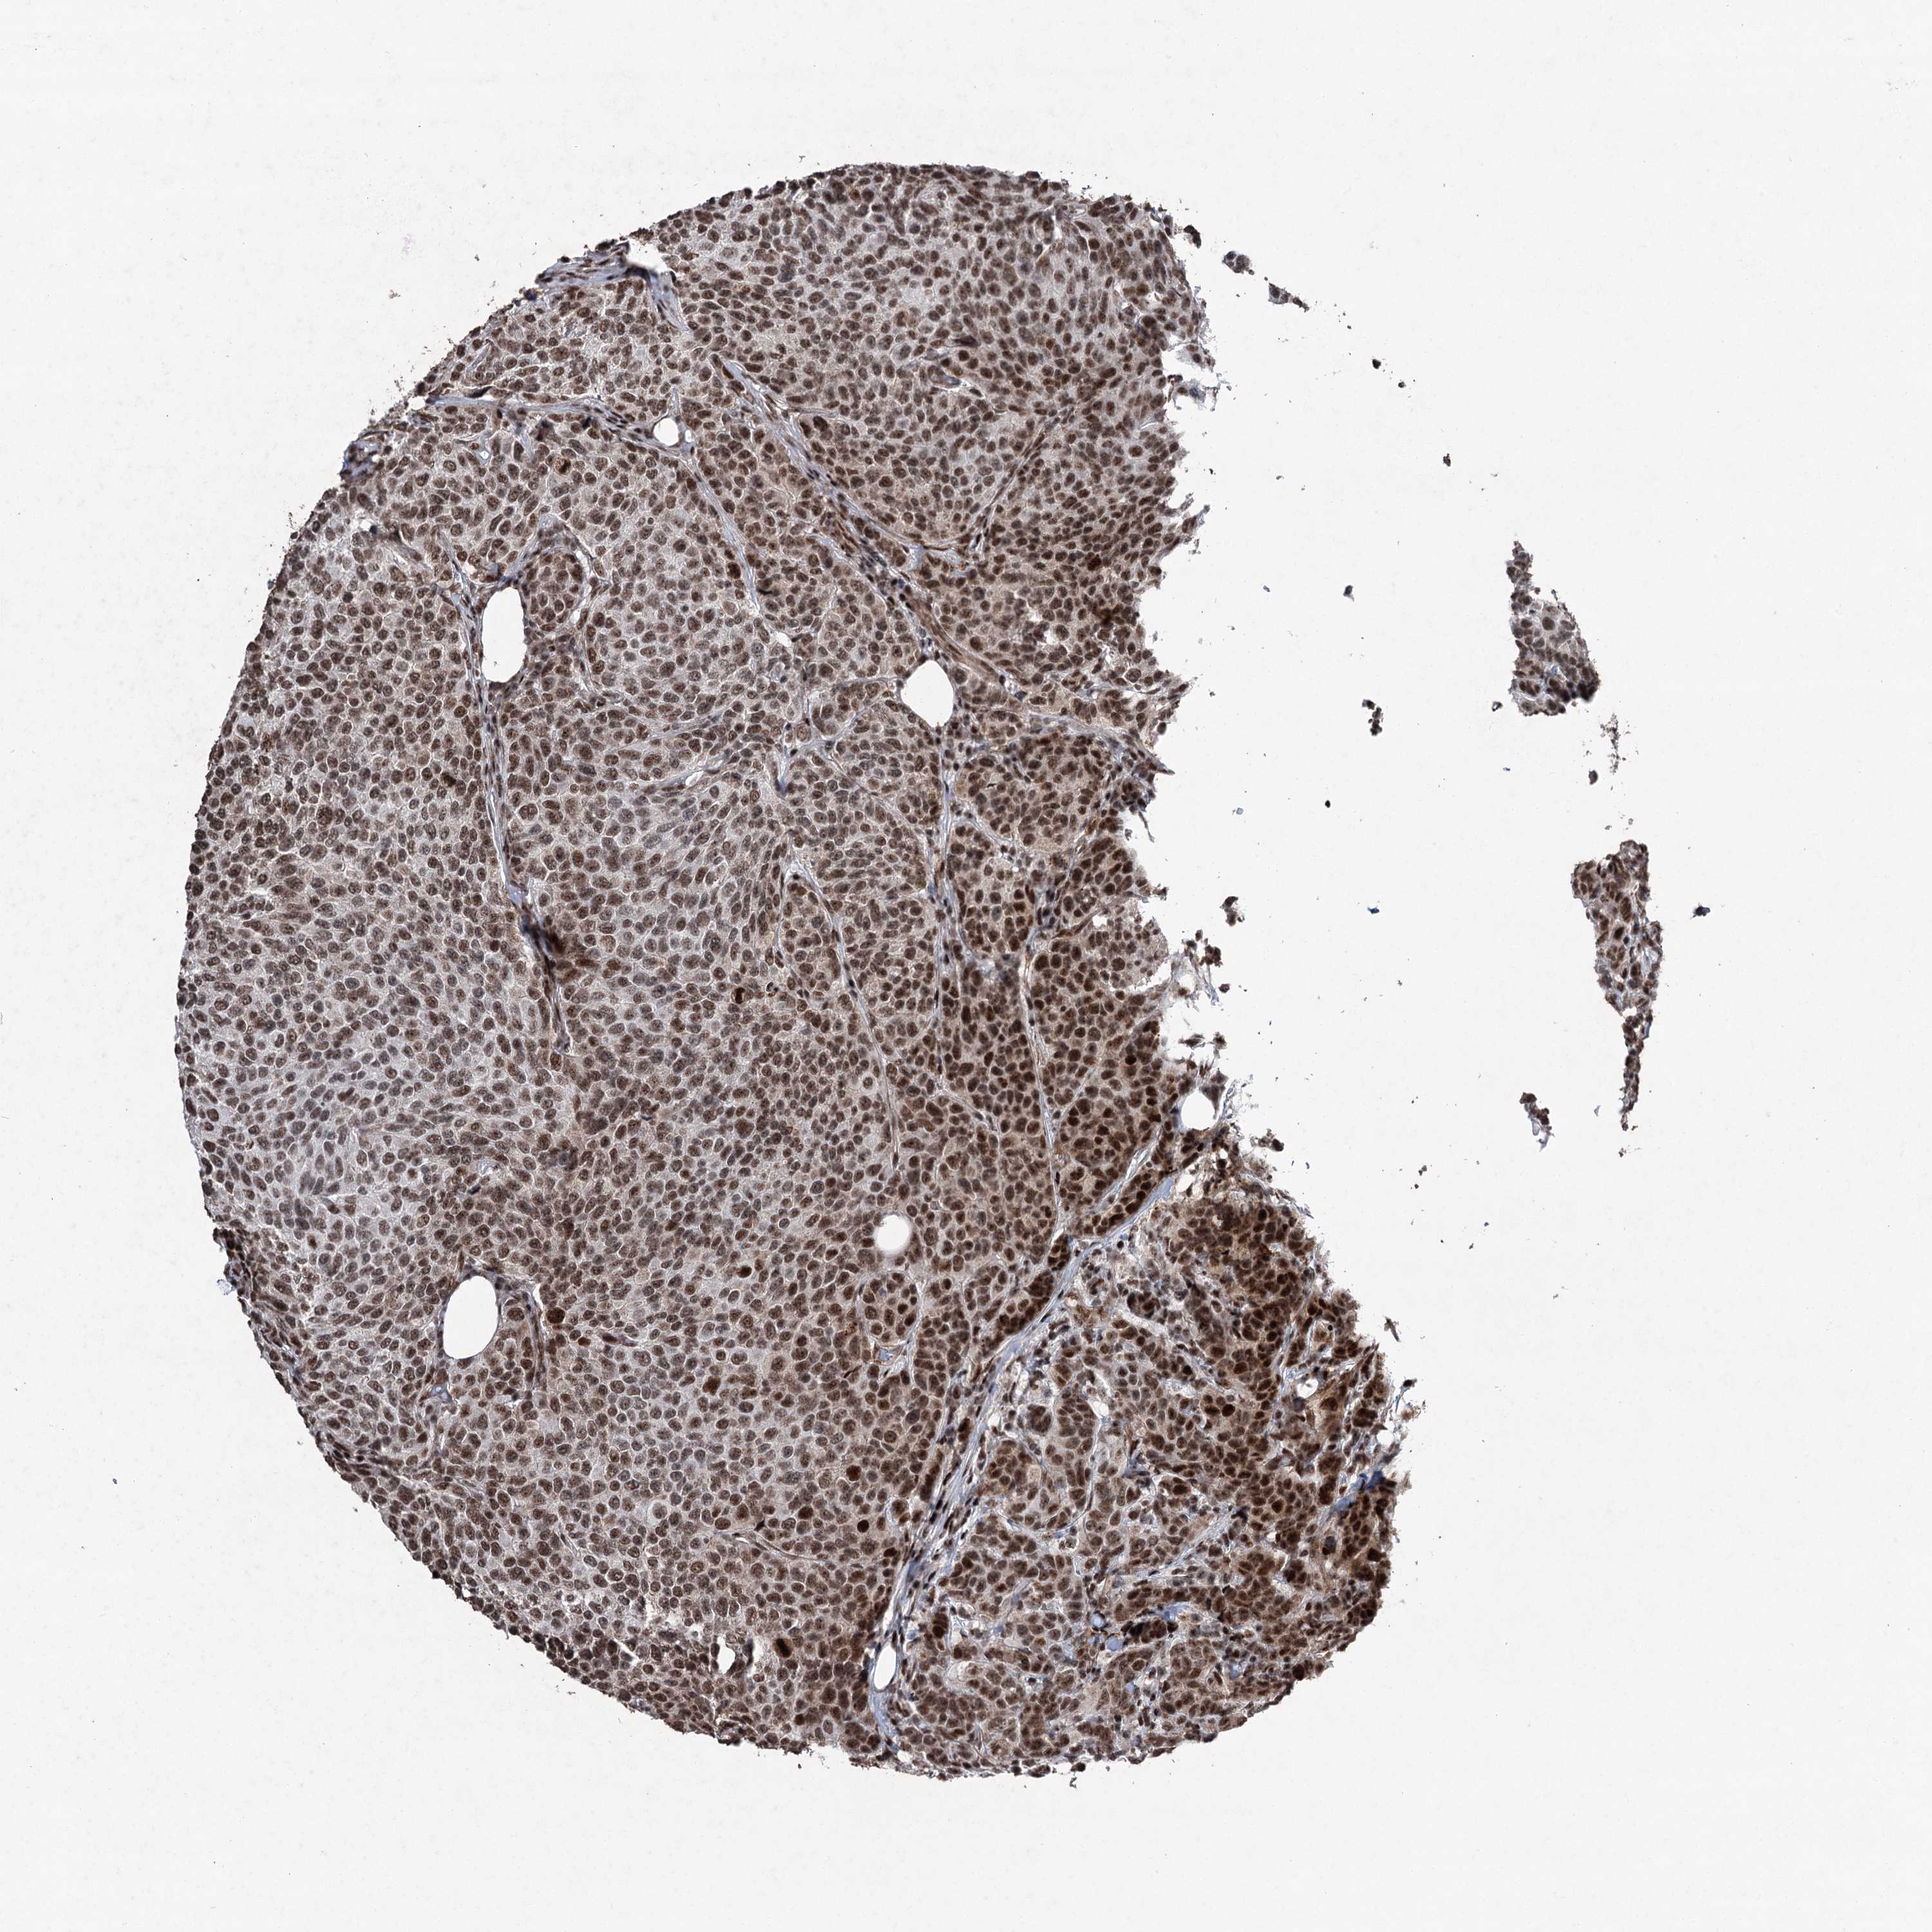

CANCER BREAST CANCER Show tissue menu

BRCA TCGA BRCA VALIDATION PROTEIN EXPRESSION